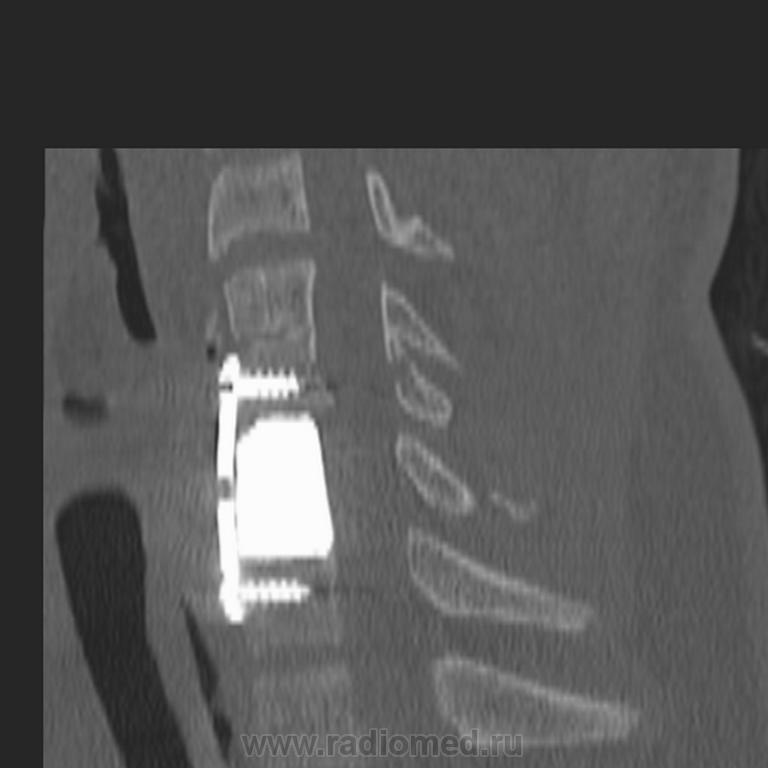

Пол пациента: Мужской пол Тип патологии: Травма Область исследования: Скелетно-мышечная система Методы исследования: КТ Снова молодой ныряльщик... Поставили имплант. Жаль, что это ему не поможет нормально жить. https://radiomed.ru/sites/default/files/styles/case_slider_image/public/user/5374/image00002.jpg?itok=P5NKASeg https://radiomed.ru/sites/default/files/styles/case_slider_image/public/user/5374/image00003.jpg?itok=DxGAT6xz https://radiomed.ru/sites/default/files/styles/case_slider_image/public/user/5374/image00004.jpg?itok=pPUmQRPJ ID:5360 Втр, 10/08/2010 - 23:18 #1 Сергей Нагорный Не на сайте Был на сайте: 9 лет 8 месяцев назад Зарегистрирован: 13.07.2010 - 22:49 Публикации: 1370 Не добавились снимки, еще разок...Приложения: С уважением, С.Н. Нагорный Ср, 11/08/2010 - 16:19 #2 Vikkur Не на сайте Был на сайте: 4 года 7 месяцев назад Зарегистрирован: 24.09.2009 - 14:34 Публикации: 1749 Что тут позвонок "треснул"? или имплант сломался? Виктор.

Что тут позвонок "треснул"? или имплант сломался?